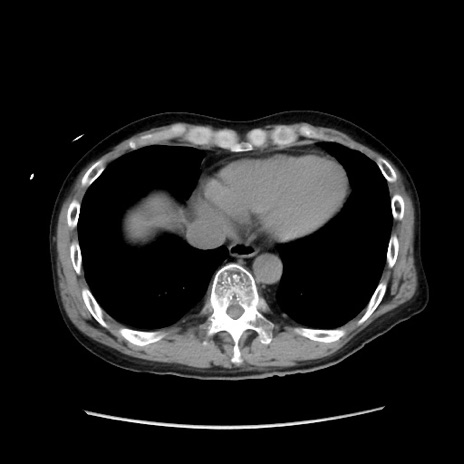

症例37(横断像)

【症例】40歳代 男性

【主訴】腹痛

【現病歴】4時間ほど前に電車に乗車中に臍部上より腹痛出現。徐々に増悪し起立困難となり、救急外来受診。生ものは数日食べていない。今朝お雑煮を食べた。

【身体所見】BT 36.8℃、BP 117/84mmHg、HR 91/min、SpO2 97%、苦悶様、腹部:臍上部広範囲圧痛あり、反跳痛±

【データ】WBC 8100、CRP 0.03